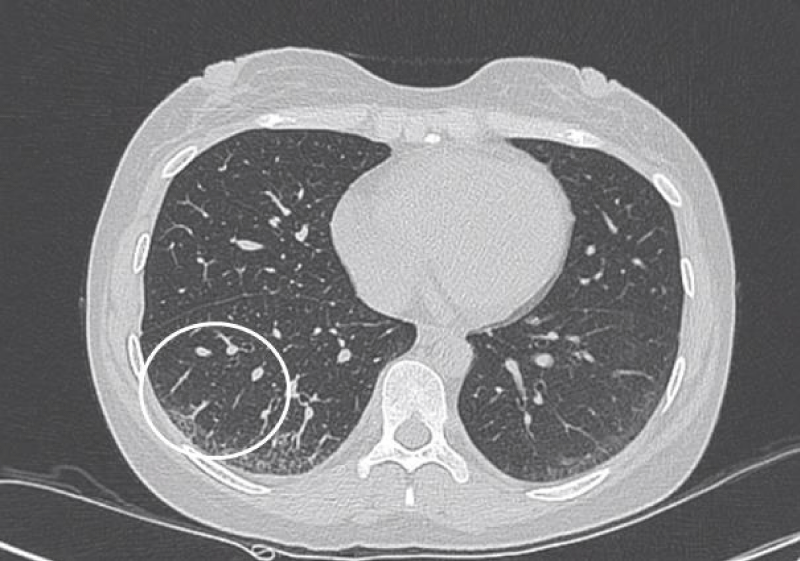

HRCT images

The most common presentation on HRCT were ground-glass opacities, showed 79.3% (92 patients). Secondly, 74.1% patients showed interlobular septal thickening, followed by reticular opacities(58.6%), intralobular interstitial thickening(45.7%), mediastinal lymph node enlargement(36.2%), nodules(30.2%), honeycomb cysts (29.3%), traction bronchiectasis(21.6%), stripes(17.2%), pleural thickening(14.7%), pleural effusion(10.3%), dilation of the esophagus(6.9%), emphysema(6.9%), bullae(5.2%), consolidation(5.2%), subpleural line(0.9%) (Figures 1-9).

Figure 9: Different levels HRCT images from a 52 year-old male considered as LIP pattern.

The most common pattern in SSc-ILD was NSIP, accounted for 71.6% (83 patients); secondly was UIP, accounted for 25.9%, and 3 patients presented consistent with LIP.

The pathological characteristics of lymphocytic interstitial pneumonia (LIP) were diffuse interstitial lymphocyte infiltration and interlobular septal thickening. The feature of HRCT was the thin-walled (pellicle) cysts scattered in ground-glass opacities diffusely at both lungs [4].